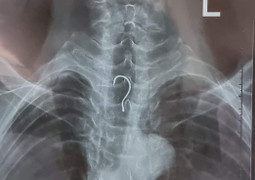

BSCKI Nguyễn Trung Độ - khoa Mắt, Trung tâm Y tế huyện Vân Đồn cho biết - bệnh nhân đến trung tâm trong tình trạng tỉnh, mắt phải mi sưng nề, dị vật mi móc câu đâm ngập 1/3 chiều dài.

"Lưỡi câu đi sâu và bám chắc vào phần sụn mi mắt trên bên phải của bệnh nhân, may mắn là nhãn cầu chưa bị tổn thương", bác sĩ Độ nói.

Lưỡi câu được rút ra thành công với phần ngạnh nằm sâu trong mí mắt gần 1cm. Đường rạch ngắn, được bác sĩ khâu lại theo giải phẫu nhằm đảm bảo thẩm mỹ cho bệnh nhân.